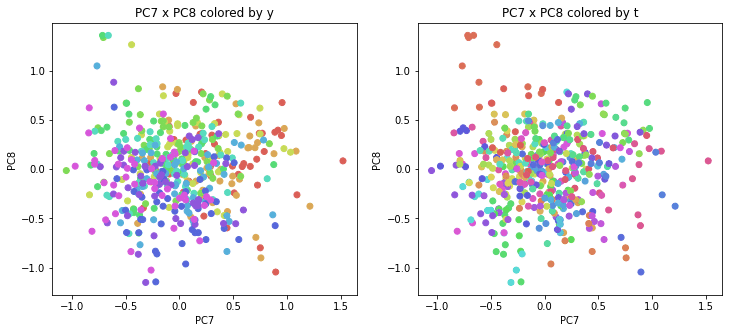

PCAの結果の第n主成分をPCnと表記します。

医療費データの場合と同様に、PCAの結果を見やすく表示するため、seabornのカラーパレットを使って、年月別、都道府県別に色分けして図示してみます(左側が年月別に色分け、右側が都道府県別に色分け)。PC1~PC8まで表示しました。

医療費データの場合ほどはっきりとはしていませんが、PC2が概ね時間の経過を表す成分で、残りの成分が時点によって変わらない地域の特徴を表す成分となっているようです。

また、PC1×PC3を見ると、47沖縄が他の都道府県からかなり離れたところに位置しており、沖縄の地域差が際立っているのが分かります。これは、以前別の記事で年齢階級のない健診データでPCAを実行した場合と似た結果となっています。